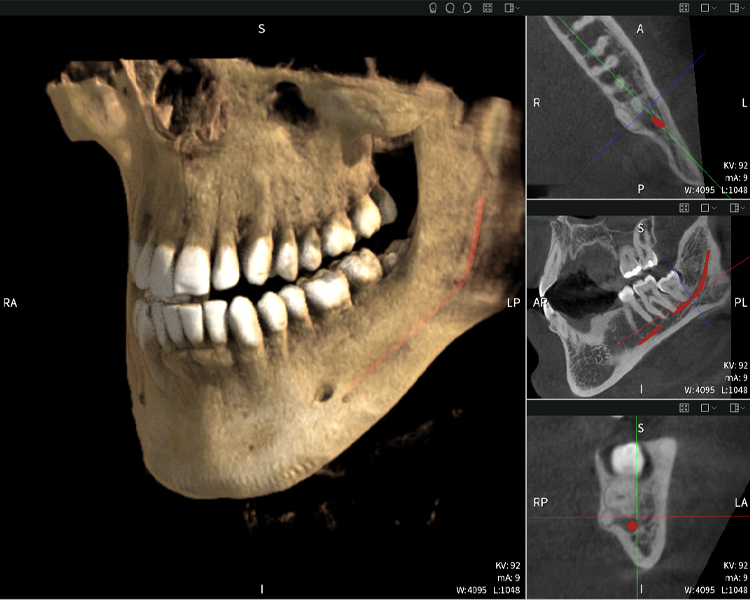

Figures b–d show various views of a 3D reconstruction of the mandible, providing a comprehensive overview of the mandibular anatomy, the position of the nerves in relation to the teeth, and allowing assessment of tooth symmetry and alignment.

Figure d shows the previously treated tooth 48, with its crown removed, and its roots left in proximity to the nerve, illustrating the high risk of nerve damage.